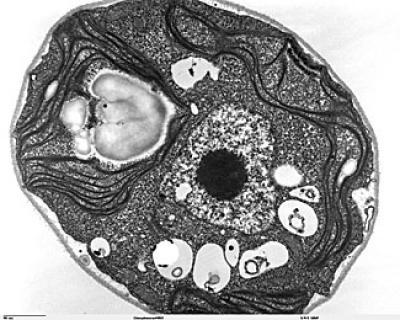

An electron microscope image of a mammalian cell with organelles depicted. In autophagy, some elements of a cell are degraded and recycled to generate nutrients and energy to sustain and preserve the whole cell.

(Photo Credit: UC San Diego School of Medicine)